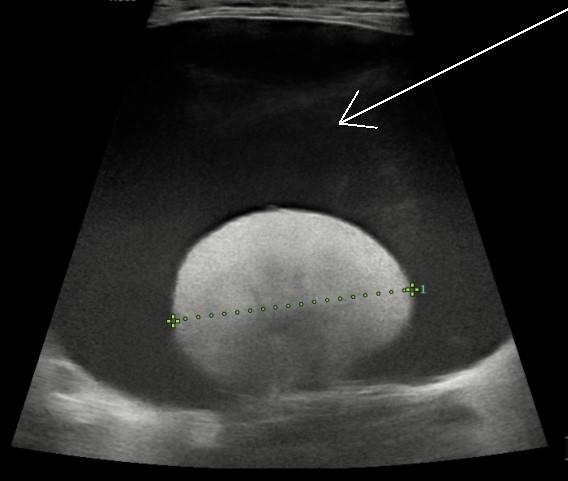

“Investigations, including an abdominal ultrasound and blood tests, revealed Micki had large perirenal cysts, which are fluid-filled structures surrounding the kidneys.

“The cysts were very large indeed and were identified as the likely cause of the discomfort and decreased appetite. Our first course of action was to drain the cysts of their fluid to reduce their size and impact on Micki.

“We received an appointment at Willows within a couple of days and Micki underwent an ultrasound scan, with Lucy confirming what she said was a rare diagnosis.

“Draining the cysts was discussed and, after consideration, we decided to go ahead with the procedure, with 1.5 litres removed from around her kidneys.